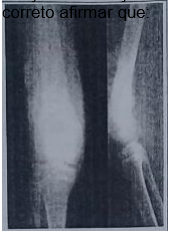

Menina de 11 anos, com história de aumento de volume em joelho direito iniciado há 65 dias não tendo procurado facultativo. Apresentou queda da própria altura inadvertida onde evoluiu com dor em MID e piora do edema inicial, além de refratariedade à analgesia convencional domiciliar. Genitora relatou perda ponderal de 2kg no período. Neste momento procurou facultativo que solicitou as imagens radiográficas ao lado. Em relação à descrição radiológica, suspeita diagnóstica e propedêutica confirmatória, é correto afirmar que: